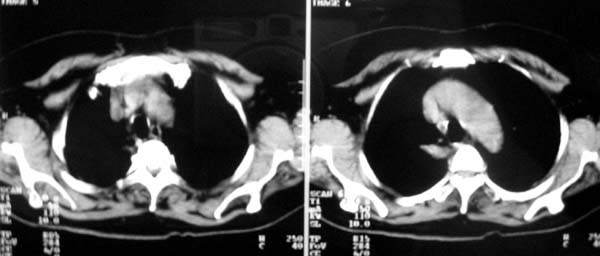

以下是引用zjzjr在2007-8-30 22:22:00的发言:[br]右上肺肺囊肿合并感染.右下肺肺大泡.左肺舌段感染.

以下是引用天南地北在2007-8-30 23:19:00的发言:[br][quote]以下是引用zjzjr在2007-8-30 22:22:00的发言:[br]右上肺肺囊肿合并感染.右下肺肺大泡.左肺舌段感染.